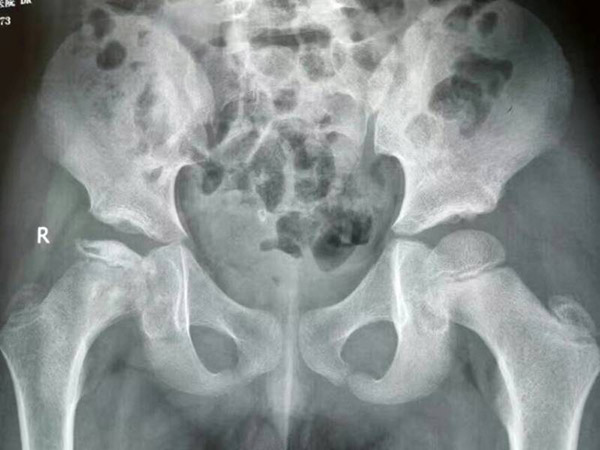

治疗前